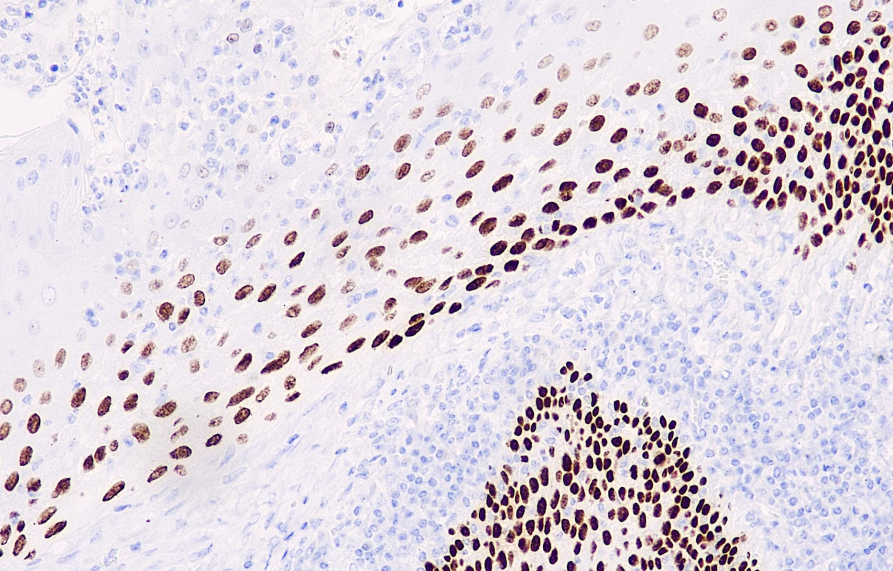

Cellular localization: nucleus

Positive control: tonsils

p63 is a homologous gene of the tumor suppressor gene p53, located on chromosome 3q27-28, encoding more than six isomers, which respectively possess transcriptional kinase activity, death induction activity (TAP63), and chromogenic inactivation activity. It is highly expressed in the basal layer of many epithelial tissues. It is expressed in myoepithelial cells of all normal mammary glands, partially in ductal proliferative cells, and in very small amounts in breast cancer in situ. It is not expressed in invasive ductal carcinoma. The absence of p63 expression may have a certain correlation with the progression of ductal carcinoma of the breast. Therefore, p63 immunohistochemical staining is helpful for the study of invasive ductal carcinoma of the breast, ductal carcinoma in situ, and a small number of suspected ductal hyperplastic injuries and other diseases. Recent studies have shown that p63 serves as a reference for prostate basal cells, but it is not expressed in the vast majority of prostate tumors. This antibody is mainly used in the research of benign and malignant lesions of the breast and prostate.

The p63 antibody reagent can specifically bind to the p63 molecular antigen. The immunohistochemical reagent kit containing the p63 antibody reagent is suitable for the precise diagnosis of head and neck squamous cell carcinoma, lung squamous cell carcinoma and breast triple-negative carcinoma, etc.